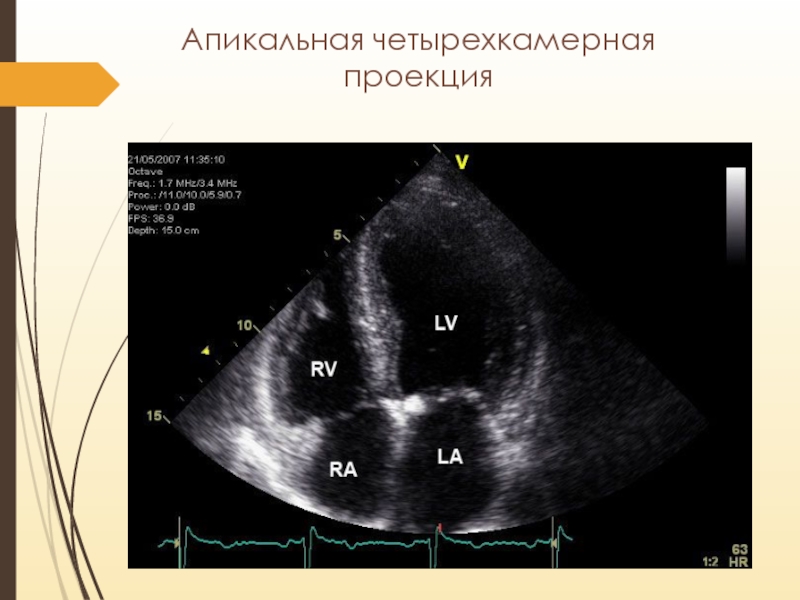

Слайд 9Апикальная четырехкамерная проекция

Апикальная четырехкамерная проекция